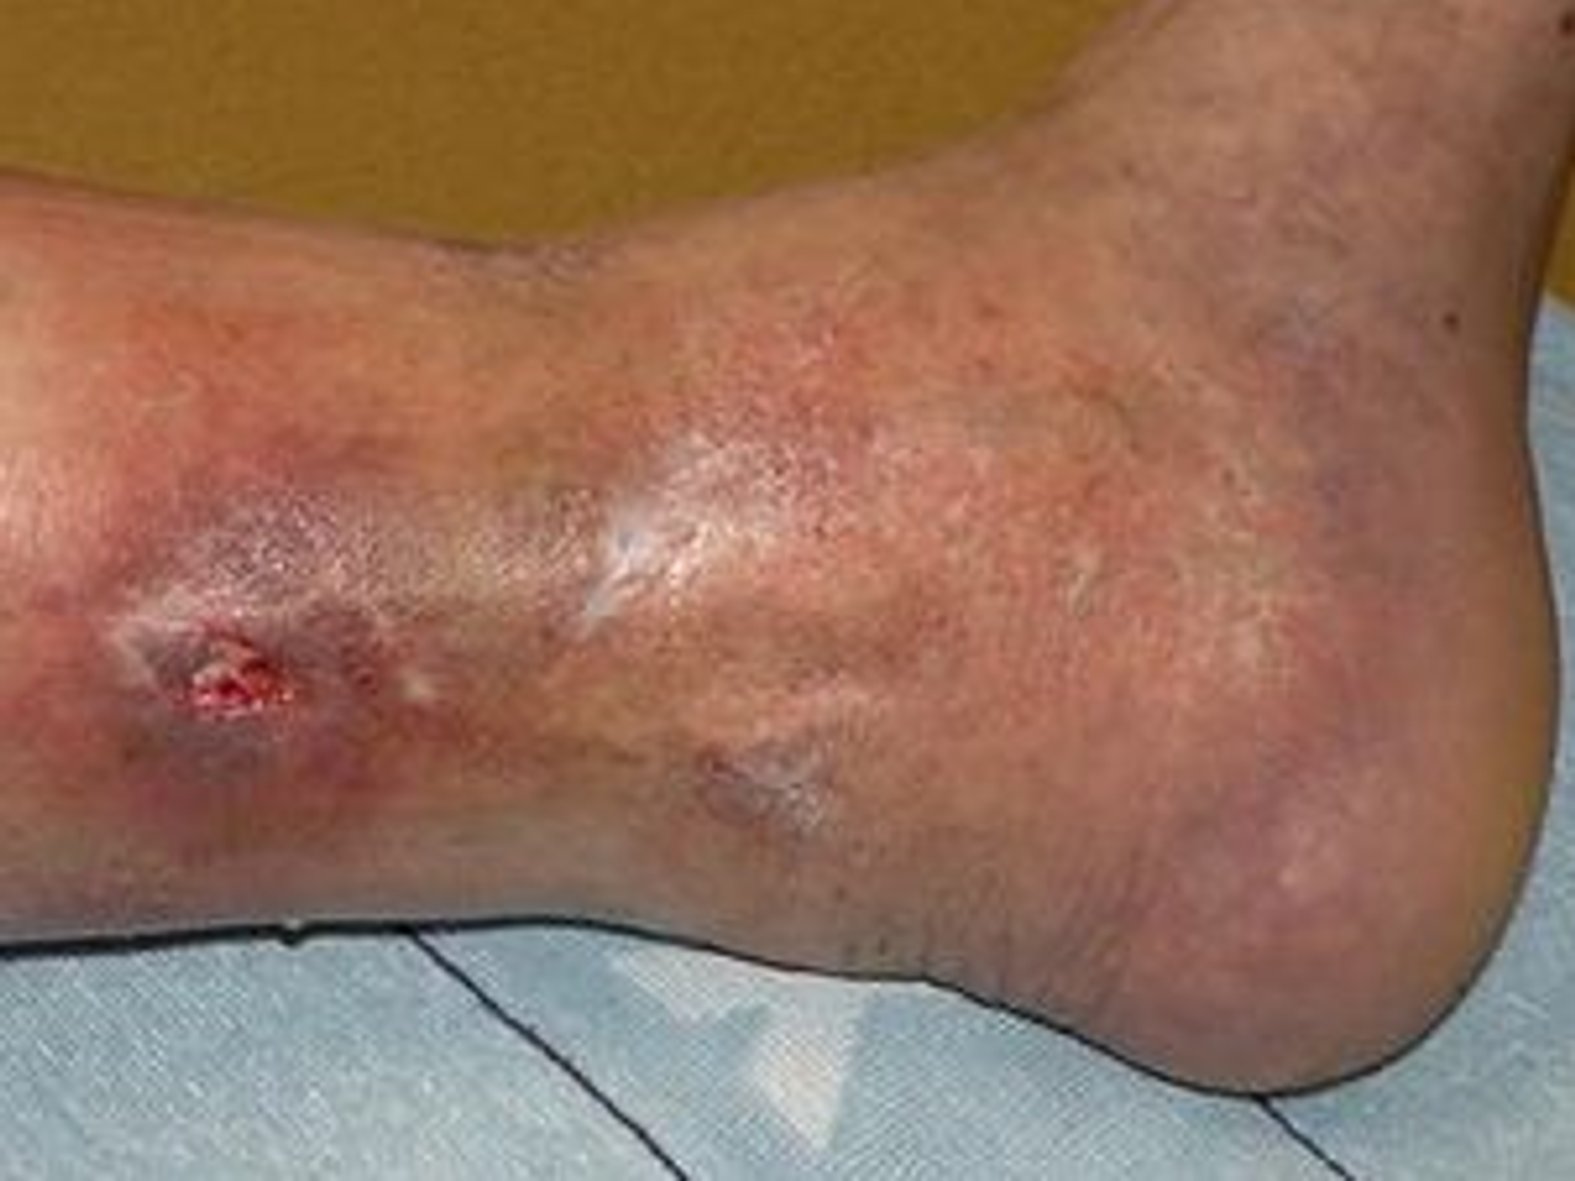

Fallbeispiel: Ödematöser, mazerierter Wundrand bei chronisch-venöser Insuffizienz

Stark exsudierende Wunde Tag 1

Der Wundrand der in diesem Fallbeispiel behandelten Wunde war mazeriert und zudem ödematös. Lesen Sie hier den dokumentierten Wundverlauf, der letztendlich zur Heilung der Wunde führte.

Mazeration am Bein

Bild 6: Mazeration am Wundrand